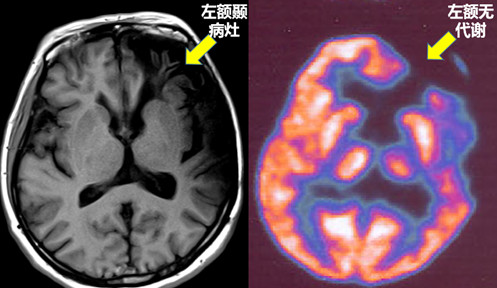

影像后处理之影像融合

什么是影像融合?影像融合:多源信道采集的关于同一目标的图像(CT、MRI、PET等),经过图像处理,提取各自信道的信息,综合成同一图像以供观察或进一步处理。为什么需要影像融合? 在我们中心大量的手术病